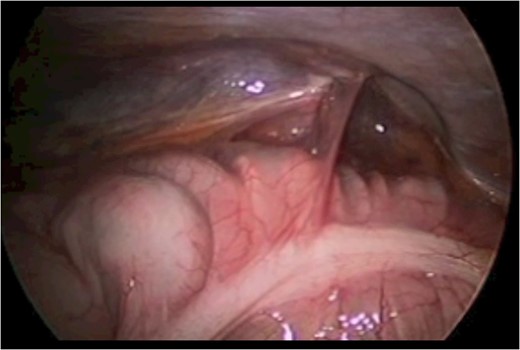

A 43-year-old male patient presented with a right-sided traumatic lumbar hernia after a blunt mechanism. The patient had been pinned between a dirt-mover’s claw arm resulting in a crush mechanism. He sustained injuries to the lumbar spine, sacrum, abdominal wall and 12th rib. On presentation, he did not have clinical or radiographic evidence necessitating abdominal exploration and was observed in a monitored setting. Computed tomography imaging demonstrated a Grynfeltt defect with herniation of the ascending colon and cecum through an area defined by the 12th rib, quadratus lumborum and internal oblique (Figures 1 and 2). After several days of observation and recuperation, the patient continued to have significant pain overlying the hernia site. We electively brought him to the operating room on post-injury Day 4. A laparoscopic repair of the traumatic hernia was performed. Key operative steps included: (i) Wide exposure of the hernia defect via incision of the peritoneum and transversalis as well as mobilization of the ascending colon and duodenal sweep (Figures 3 and 4). (ii) Primary repair of the defect with intra-corporeal suturing of the oblique musculature (Figures 5 and 6). (iii) Placement of an underlay mesh with appropriate redundancy at least 4 cm in all directions around the defect and seating against the iliac crest (Figure 7). Post-operative imaging demonstrates obliteration of the hernia defect and restoration of the abdominal wall (Figures 8 and 9). The patient has recovered, returned to the work force and has no pain or bulge at the repair site 6 months after injury.

Step 1 begins with incision of the peritoneum overlying the hernia.